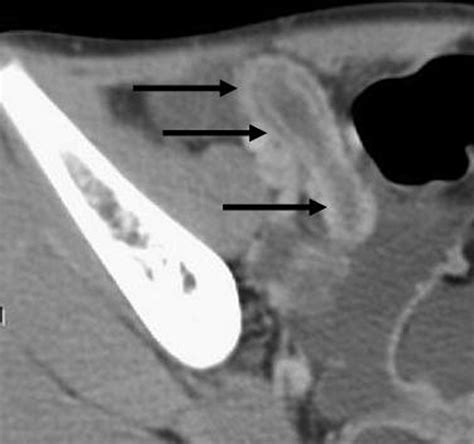

• Appendicoliths: These are calcified deposits (fecal stones) within the appendix that can obstruct the lumen, leading to infection.

⚠️ Note: The presence of an appendicolith is often associated with a higher risk of appendiceal rupture, requiring prompt surgical consultation.

These findings dictate the treatment plan. While an appendectomy (surgical removal) is the standard treatment for simple cases, complicated cases—such as those involving a large abscess—might initially be managed with intravenous antibiotics and, in some cases, percutaneous drainage guided by imaging, before a definitive surgery is performed later.